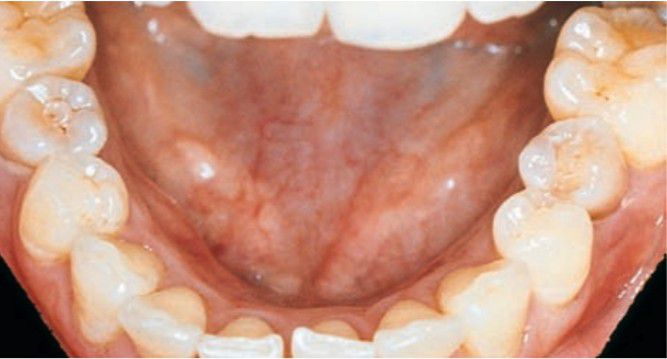

Dens evaginatus of mandibular 2nd premolars

Dens evaginatus is a relatively common developmental condition affecting predominantly premolar teeth (Leung’s premolars)